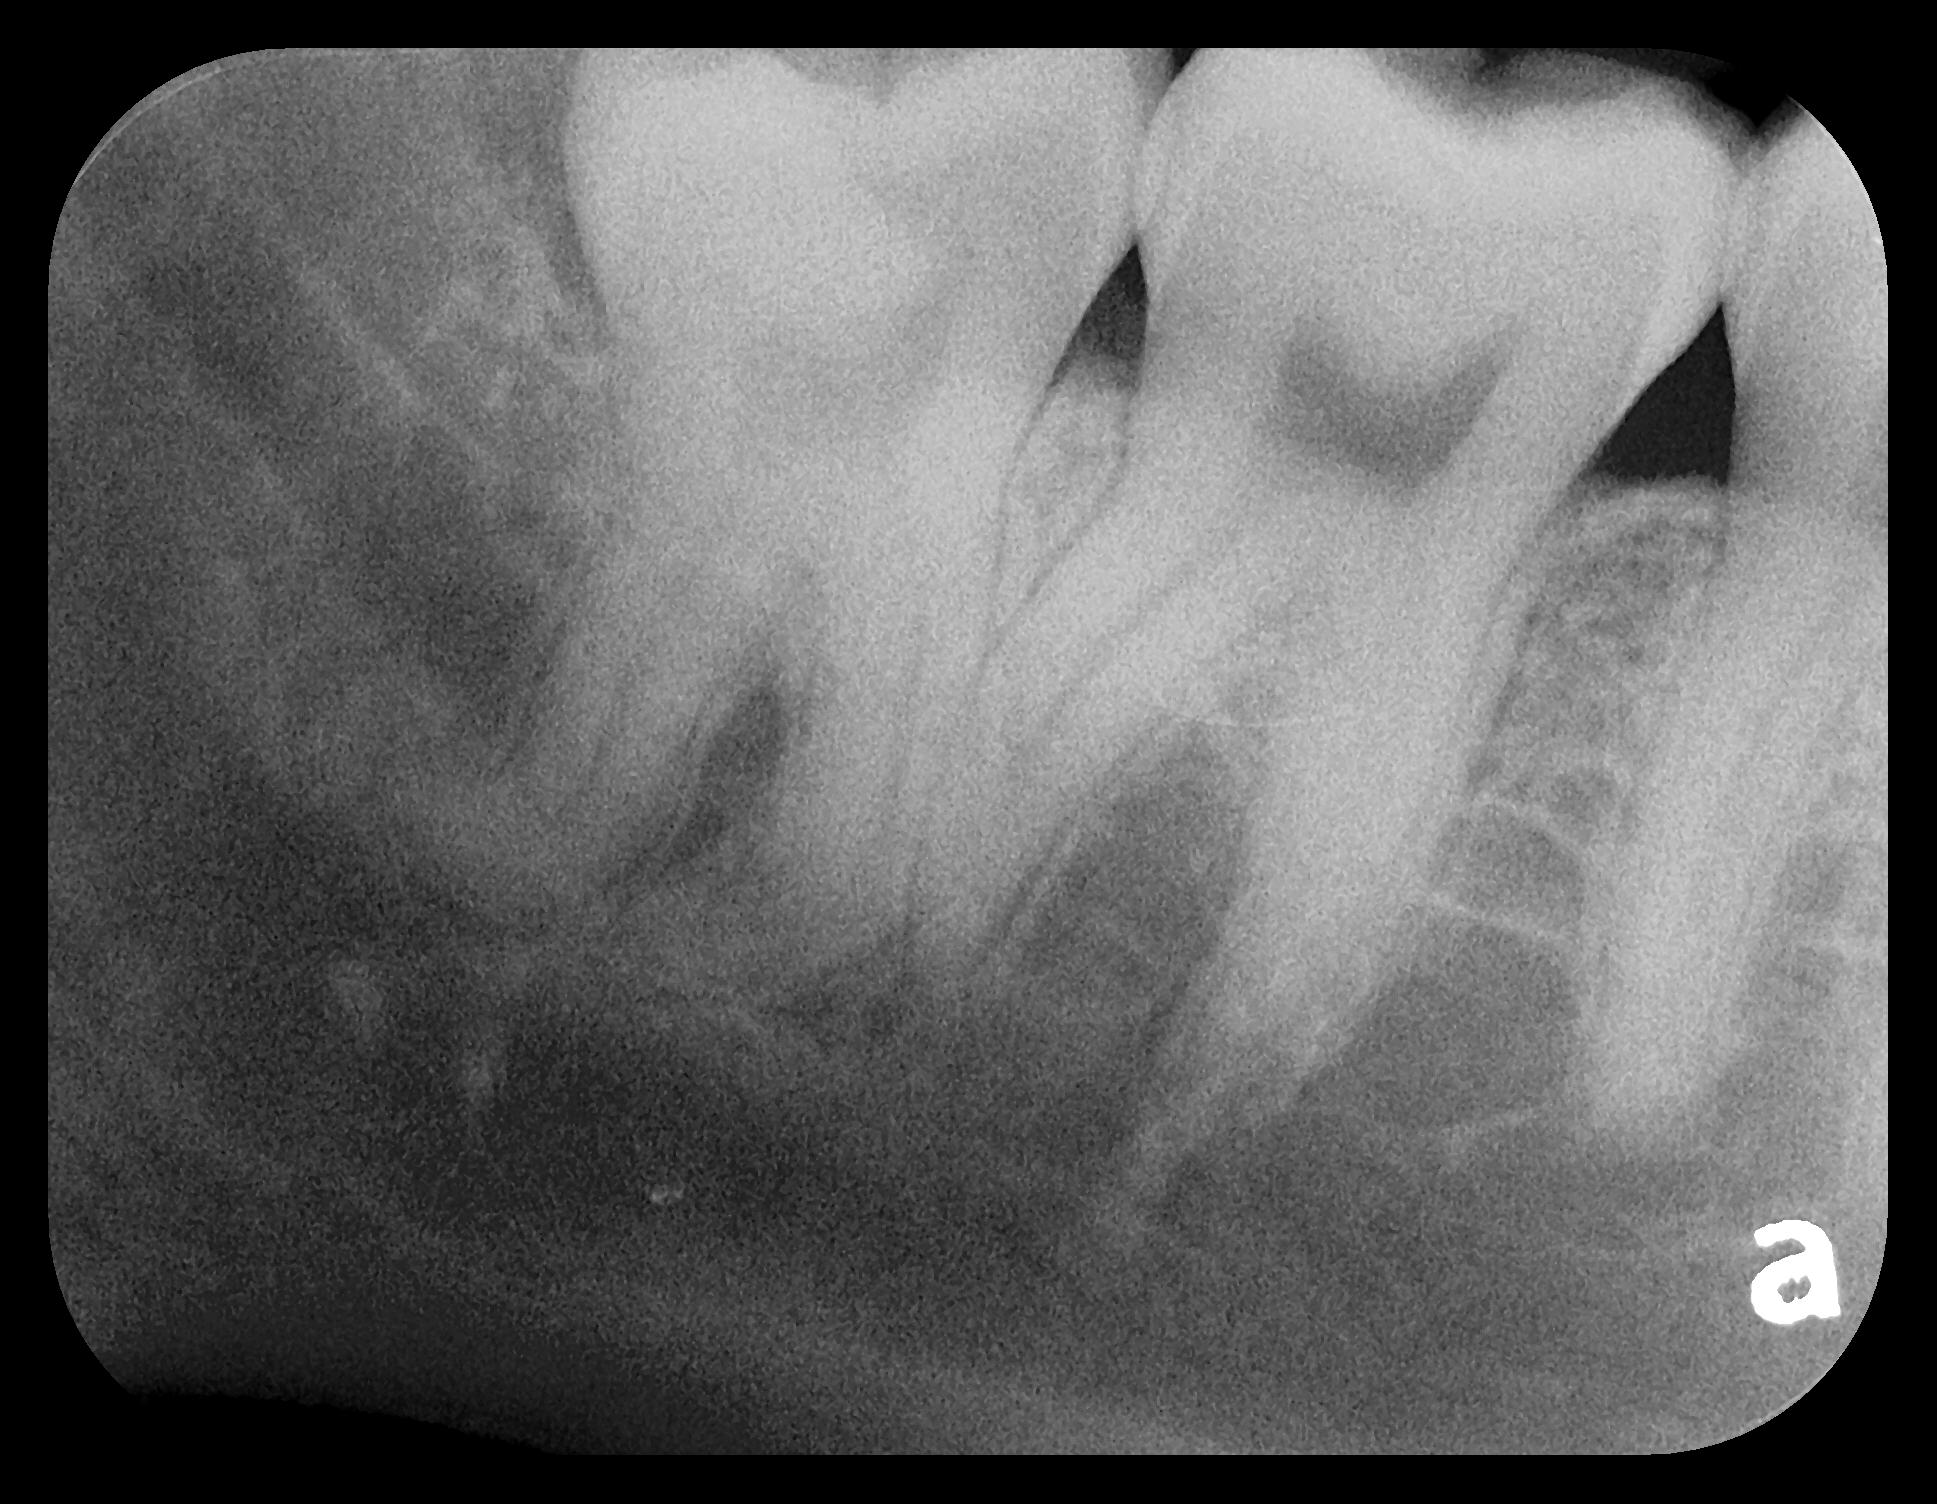

Fig 3. Two PSP PA radiographs of mandibular teeth showing: left, the initial view

of molar area and suspected pathology surrounding impacted tooth No. 32; center,

subsequently exposed PA radiograph, placed more distally, demonstrates extent

of large cyst as well as entire tooth and root No. 32. Proper alert as to presence

of suspected cyst and appropriate referral for 3D CBCT study and surgical

enucleation was given to the patient. Right: Same radiograph as on the left, but

with lighter superimposed outline of the area that would be visible using an HW

sensor rather than a PSP sensor. The small area of pathology is likely obscured

because it is visually overlaid by the root of tooth No. 31. Neglect of this significant

pathology may have resulted.

Figure 3